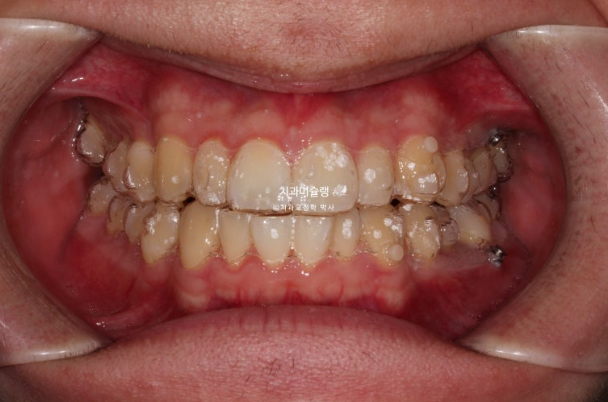

2022년 10월부터 24년 4월까지 1년반동안 첫세트 장치를 모두 낀 후 모습입니다.

24.04

가위교합은 해결이 되었지만 아직 어금니 교합이 긴밀하지 않습니다.

배열은 완벽합니다.

중심선 등을 좀 더 바로잡고자 재제작에 들어갑니다.